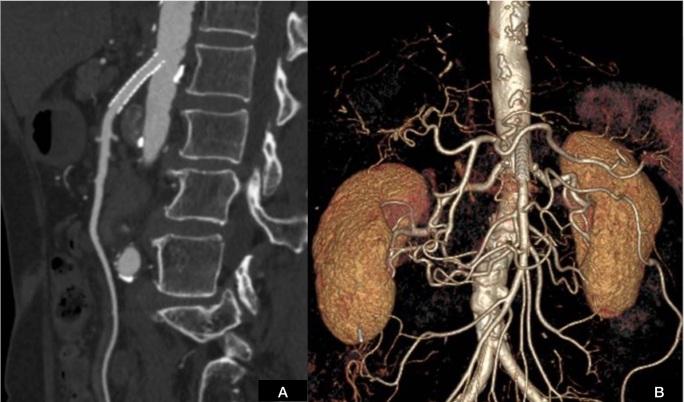

慢性肠系膜缺血导致的严重缺血性胃炎。

Severe ischemic gastritis caused by chronic mesenteric ischemia.

Ischemic gastritis is a rare illness caused by localized or systemic vascular insufficiency. This condition is rarely seen in medical practice due to the vast arterial collateral blood supply to the stomach through the celiac trunk and superior mesenteric artery and also because other etiologies are much more frequent. The classic presentation of chronic ischemia is comprises the triad of postprandial pain, weight loss, and abdominal bruit. Intervention is indicated in symptomatic patients and endovascular treatment is an alternative to surgery in patients with high comorbidity that offers good results. We report a case of a 71-year-old female patient with severe ischemic gastritis with ulcers and bleeding caused by chronic mesenteric ischemia with occlusion of the celiac trunk and inferior mesenteric artery and critical stenosis of the superior mesenteric artery. The diagnosis was confirmed by imaging, and the patient underwent endovascular treatment. This is a rare condition that is difficult to diagnose and treat and a multidisciplinary team is needed for proper management.

缺血性胃炎是一种由局部或全身血管供血不足引起的罕见疾病。由于通过腹腔干和肠系膜上动脉为胃提供了丰富的动脉侧支血液供应,而且其他病因更为常见,这种情况在医疗实践中很少见。慢性缺血的典型表现包括餐后疼痛、体重减轻和腹部血管杂音三联征。有症状的患者需要进行干预,对于合并症高的患者,血管内治疗是手术的替代方法,效果良好。我们报告一例71岁女性患者,患有严重的缺血性胃炎,伴有溃疡和出血,由慢性肠系膜缺血导致腹腔干和肠系膜下动脉闭塞以及肠系膜上动脉严重狭窄引起。通过影像学检查确诊,患者接受了血管内治疗。这是一种罕见的疾病,难以诊断和治疗,需要多学科团队进行妥善管理。